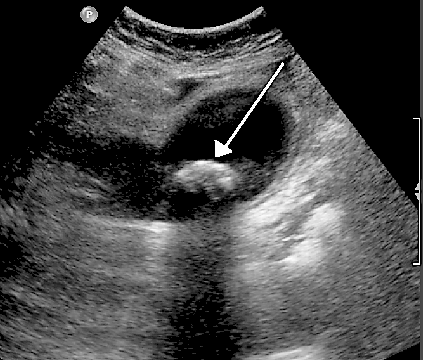

Another example is that when ultrasound travels though bile in a gallbladder it will echo back strongly if it hits a solid gallstone - as in the ultrasound image below. The arrow points to a gallstone in the gallbladder.

Gallstone ultrasound image